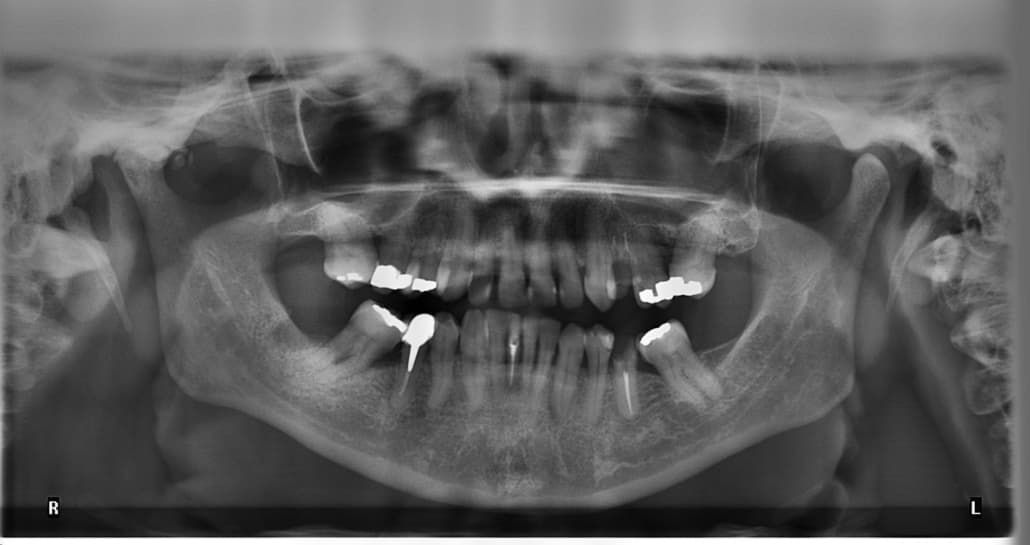

Zahnfüllung: Amalgam bleibt im Fokus der Kritik

Die geplante Prüfung eines vollständigen Verbots von Amalgam als Zahnfüllstoff basiert nicht nur auf gesundheitlichen Argumenten. Seit mehreren Jahrzehnten diskutiert man das gesundheitliche Risiko von Amalgam in Forschung und Wissenschaft. Ebenso lange steht Amalgam als Füllstoff im Fokus der Kritik. Dabei geht es um den Anteil von Quecksilber im Amalgam. Dieses Quecksilber ist potenziell zwar giftig. Doch an diesem Problem hat die Forschung beständig gearbeitet. Inzwischen setzt das heutzutage verwendete Amalgam als Zahnfüllstoff so gut wie kein Quecksilber mehr frei. Dennoch bleiben Argumente, die gegen eine Verwendung von Amalgam sprechen. Und dabei geht es nicht nur um die eingeschränkte Einsatzmöglichkeit aus optischen Gründen. Immerhin ist es nicht angemessen, Amalgam aus ästhetischen Gründen bei Frontzähnen einzusetzen.